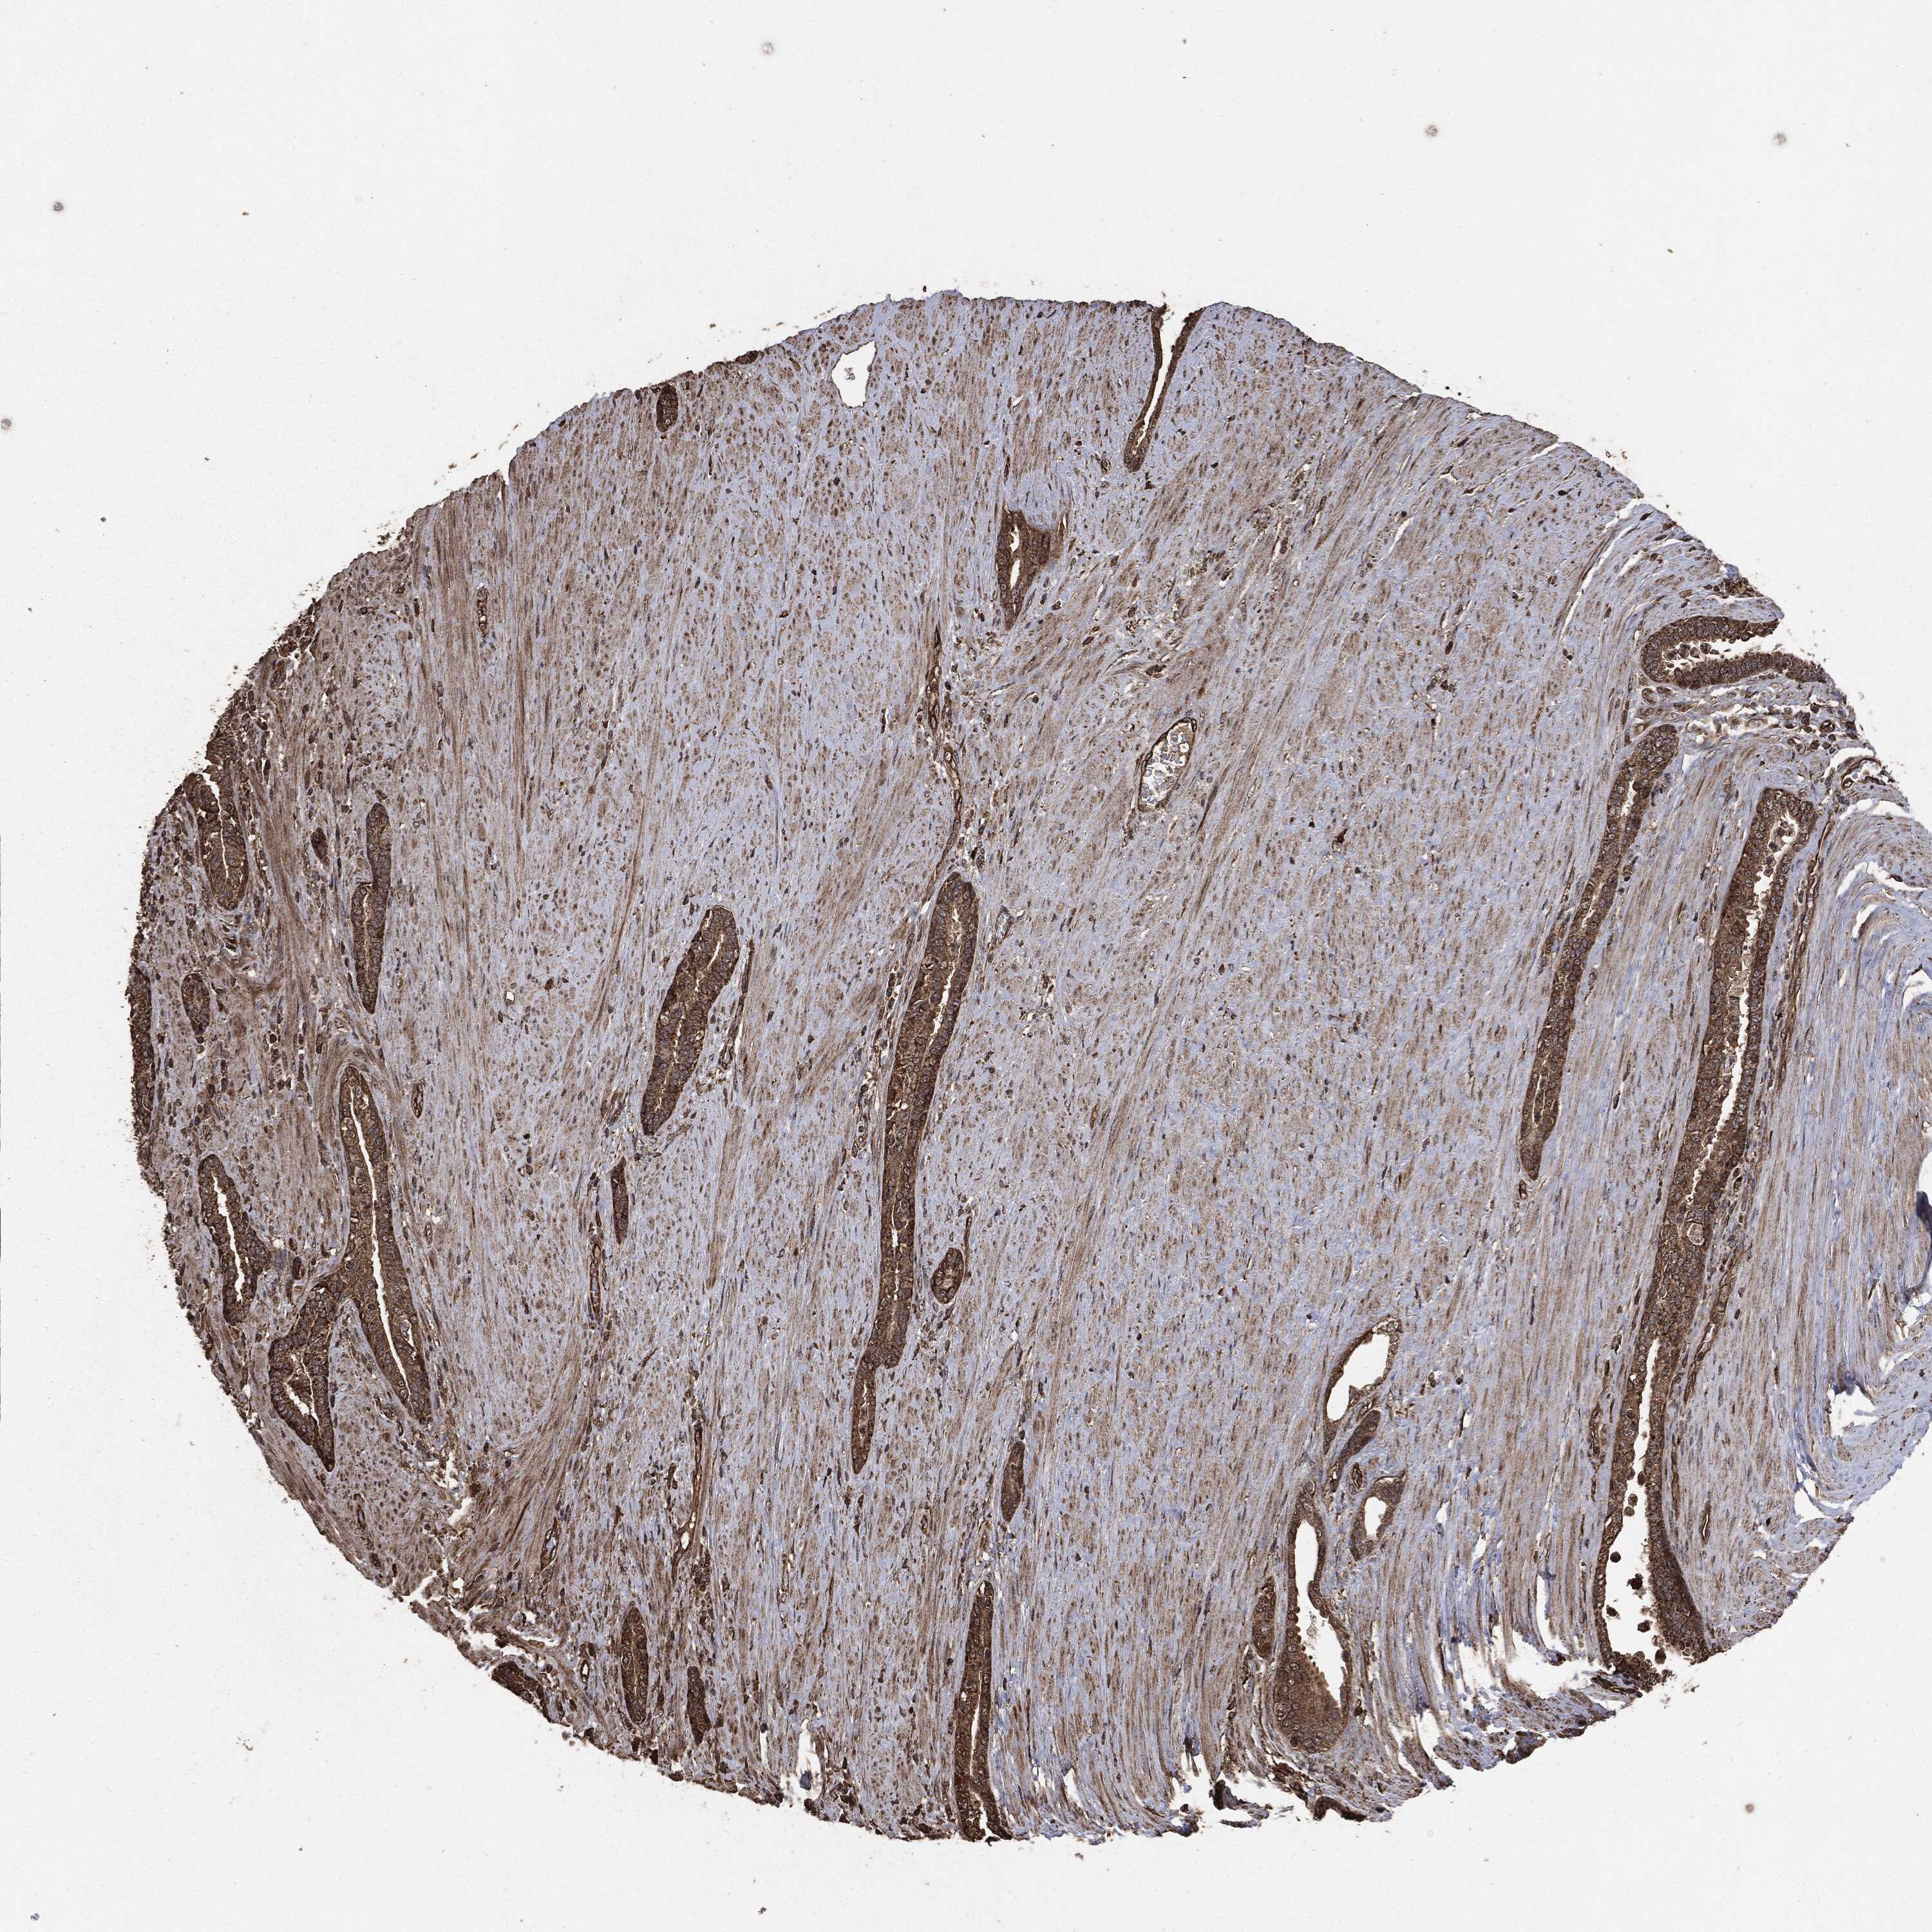

PROSTATE CANCER - Protein expressioni

A mouse-over function shows sample information and annotation data. Click on an image to view it in a full screen mode. Samples can be filtered based on level of antibody staining by selecting one or several of the following categories: high, medium, low and not detected. The assay and annotation is described here.

Note that samples used for immunohistochemistry by the Human Protein Atlas do not correspond to samples in the TCGA dataset.

Antibody stainingi

Antibody staining in the annotated cell types in the current human tissue is reported as not detected, low, medium, or high, based on conventional immunohistochemistry profiling in selected tissues. This score is based on the combination of the staining intensity and fraction of stained cells.

Each image is clickable and will lead to virtual microscopy that enables deeper exploration of all samples and also displays staining intensity scores, fraction scores and subcellular localization as well as patient and tissue information for each sample.

Adenocarcinoma, Medium grade

Adenocarcinoma, Low grade

Adenocarcinoma, High grade

Adenocarcinoma, NOS